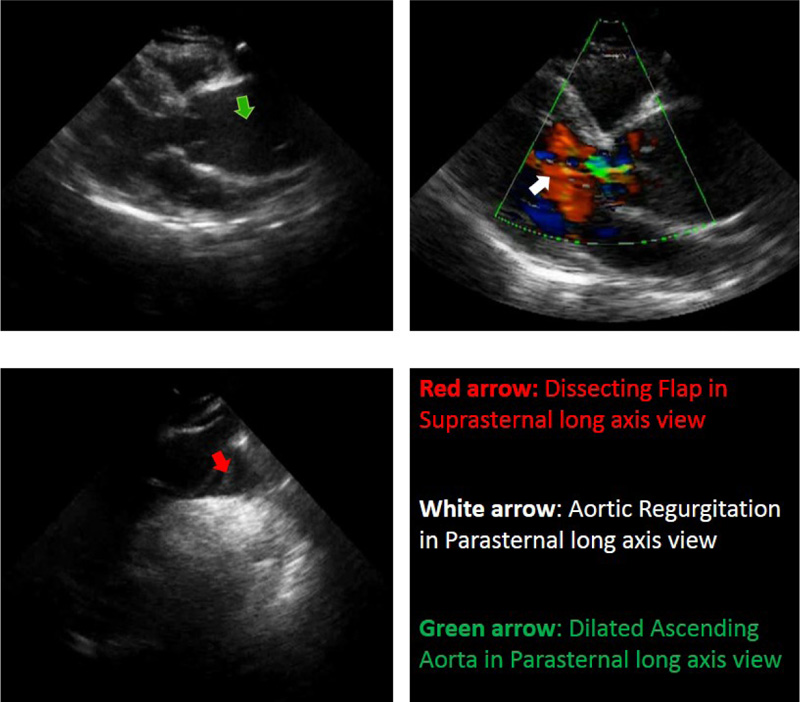

In TTE findings, evidence was in favour of type A acute thoracic aortic dissection (Fig. 2). Dilated aortic root and ascending aorta were noticed. The dissecting flap was extended from the large curvature of ascending aorta to the right brachiocephalic artery. Malcoapted AV and diastolic flow reversal in the descending aorta suggest moderate AI. The patient was immediately transferred to the CCU, and cardiac monitoring and emergency therapy were initiated. The patient was finally referred to the cardiac surgery department.

- Malcoapted AV and diastolic flow reversal in the descending aorta showed moderate AI.